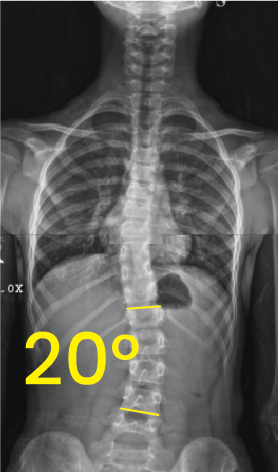

Göğüs ve bel bölgesinde 20 derece eğimli skolyozu gösteren X-ışını omurga röntgeni.Göğüs ve karın bölgesinin röntgeni üzerinde, omurga eğriliğini vurgulayan 9 derece açıyla işaretlenmiş omurga escoliosis görüntüsü.